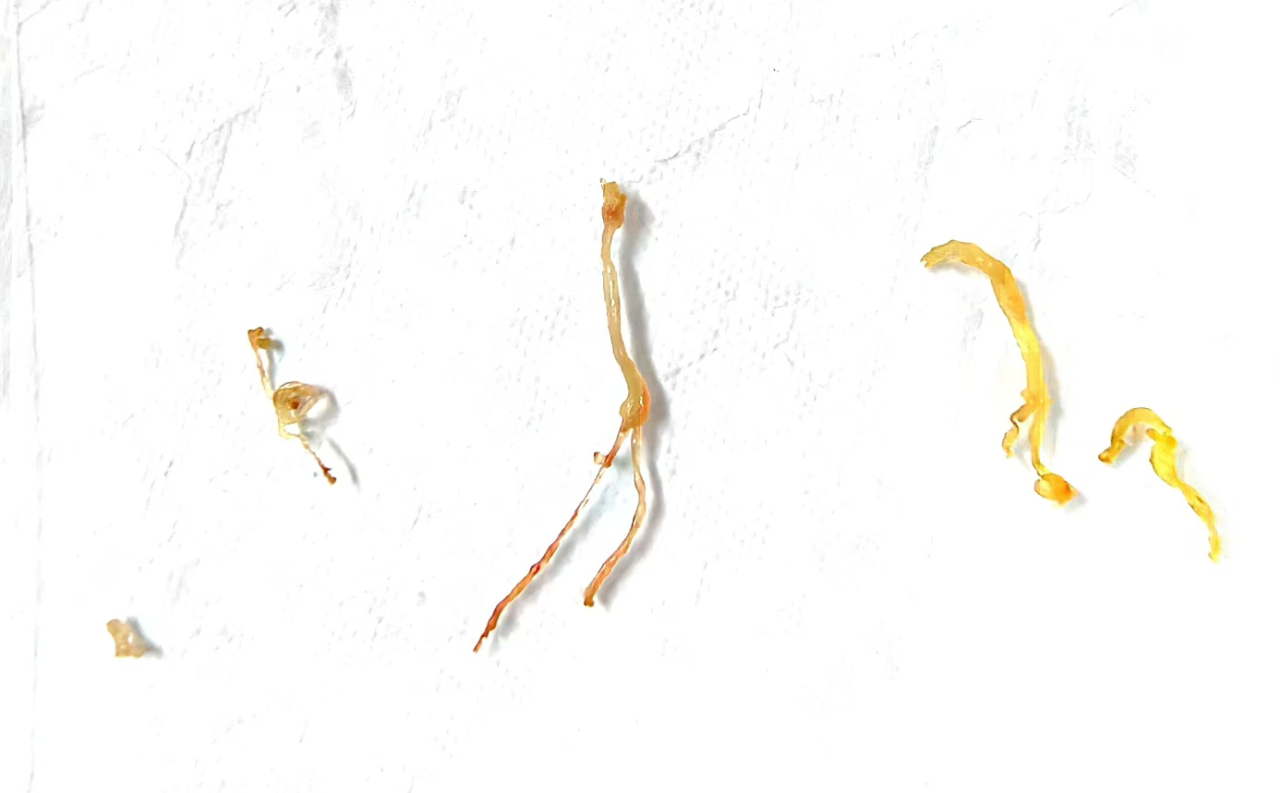

以上为取出的树枝状“塑型”痰栓

此次支气管镜介入治疗属4级手术,患儿情况复杂,无疑增加了手术难度。儿三科副主任陈明、主治医师宋德宝协助手术,麻醉医师、内镜医师默契配合,杨主任娴熟操作,准确地将支气管镜下达患儿支气管病变部位,利用取样钳一次次小心夹取痰栓,共取出6根大小不一,树枝状“塑型”痰栓,手术过程顺利。术后患儿体温恢复正常,临床症状明显改善,治疗效果显著。经进一步抗感染、抗炎等治疗,11月13日,患儿顺利出院。